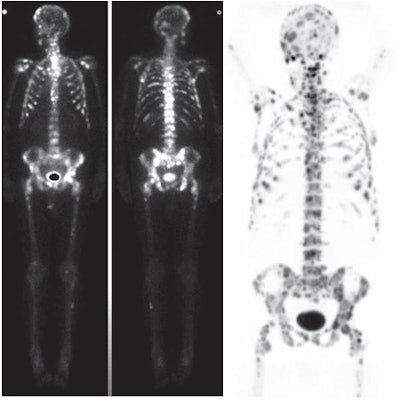

| Numerous bone metastases were detected in a 67-year-old man with prostate cancer. Bone scintigraphy (left) and NaF-PET/CT (right) images show more lesions in skull and ribs than whole-body bone MRI. Images courtesy of the American Journal of Roentgenology. |

There were no false-negative results with either of the two modalities, whereas NaF-PET/CT showed false-positive results in four patients and DWI-MRI had one false-positive finding. In addition, there were no signs of metastases in 40 patients (81%) with NaF-PET/CT, compared with 43 patients (86%) with DWI. Results from these patients were true-negative findings.

In the lesion-based analysis, NaF-PET/CT detected nine true-positive lesions, compared with five true-positive lesions with DWI-MRI. There were no false-negative results with NaF-PET/CT, compared with four false-negative lesions at DWI, and there were seven false-positive findings with NaF-PET/CT, compared with two false-positive results at DWI.

Two patients with uncountable bone metastases were analyzed separately. In these patients, NaF-PET/CT showed more bone metastases than DWI-MRI.